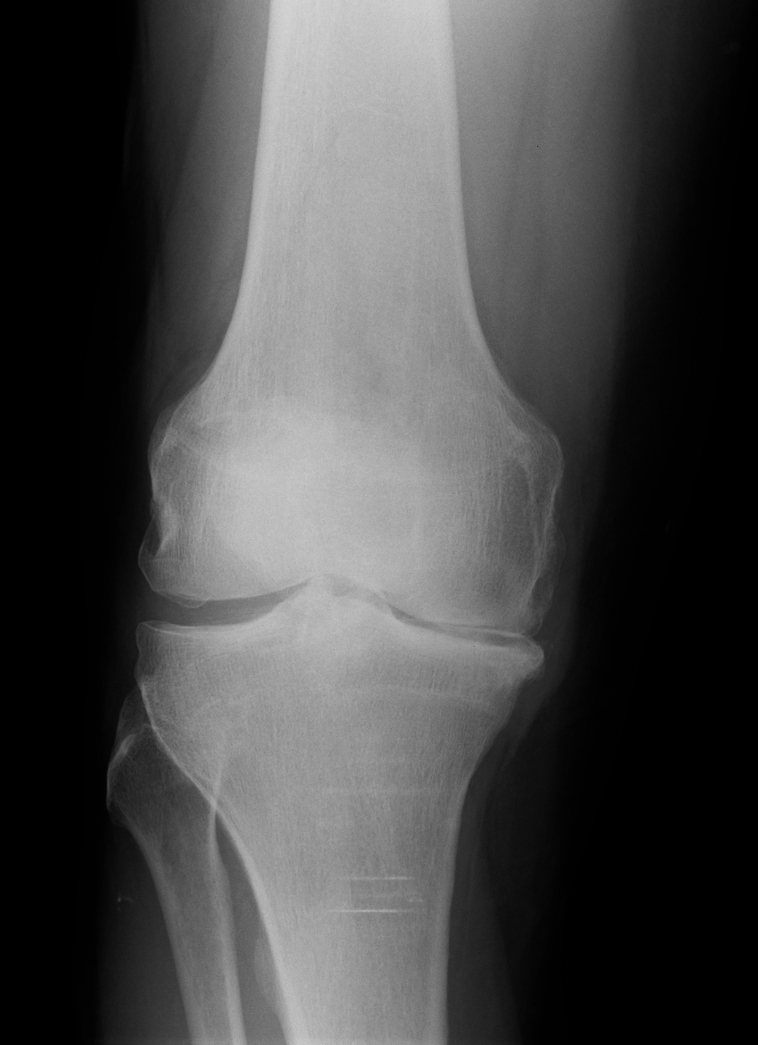

Below you see X-ray examples of patients with severe osteoarthritis of the hip before (Fig 1) and after (Fig 2) total hip replacement, and of the knee before (Fig 3) and after (Fig 4) total knee replacement that have been successfully treated under Mr Weitzel’s care.